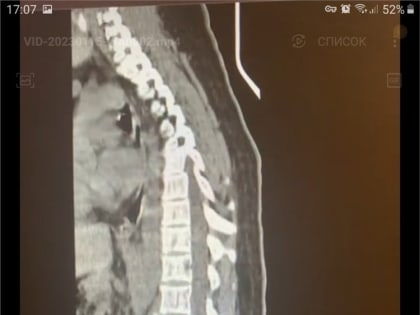

Красноярка получила травму позвоночника во время катания на тюбинге

В Красноярске врачи БСМП прооперировали молодую женщину, которая получила серьезную травму позвоночника во время спуска с горы на тюбинге.